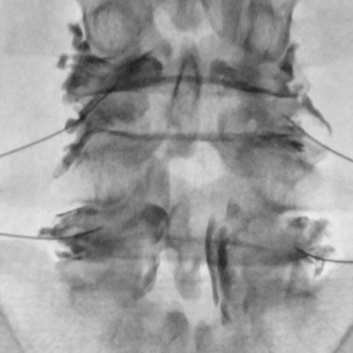

척추 통증의 원인이 되는 돌출 된 디스크나 좁아진 협착이 있는 경우 통증의 원인은 신경 주위의 유착과 부종 및 염증입니다. 경막외 신경성형술은 꼬리뼈에 있는 척추관으로 통하는 구멍으로 직경 1mm 미만의 카테터를 삽입하여 디스크와 협착증이 있는 부위까지 접근시켜 물리적으로 유착을 박리하고 화학적으로 염증과 부종을 줄여줍니다.